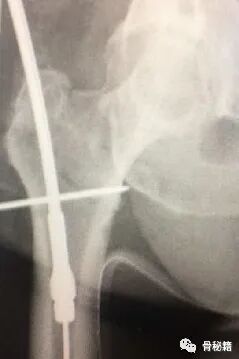

这样一个粗隆间骨折,骨折线经过入钉点,这个时候复位比较困难,及时复位,进钉的时候也很容易将骨折线撑开而造成复位不良。

1.应用螺纹导针,植入到偏前方的皮质 直达内侧的骨折块

2.将该导针套上一个套筒直达骨皮质,套筒上夹kocher钳,远端连接T把手